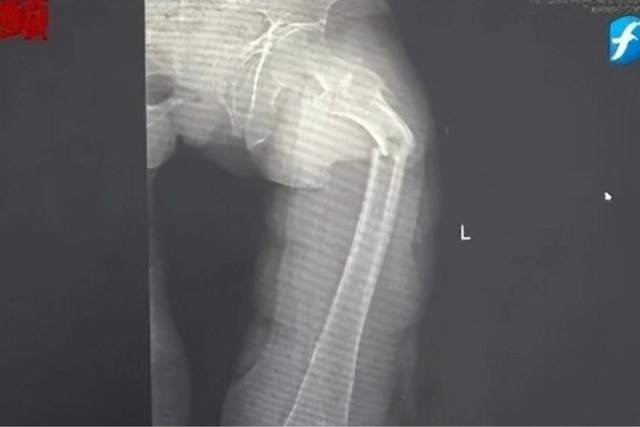

Đến nửa đêm, anh Cung bị giật mình tỉnh giấc vì cơn đau ở đùi. Anh phát hiện ra mình không thể đi lại được nhưng cố chờ đến trời sáng hẳn rồi nhờ người nhà đưa đi bệnh viện. Kết quả chụp X-quang tại Bệnh viện Nhân dân số 2 Phúc Kiến (Trung Quốc) khiến anh Cung sốc nặng: xương đùi trái của anh bị gãy làm hai mảnh.

Bác sĩ Đông Trung, Trưởng khoa Chấn thương và Chỉnh hình của bệnh viện cho biết anh Cung bị gãy xương bệnh lý, xảy ra do loãng xương sớm rất nghiêm trọng. Dù mới 35 tuổi nhưng xương của anh Cung được bác sĩ nói vui là "xốp như tổ ong", khối lượng xương tương đương với một cụ già 80 tuổi.

Hình ảnh xương đùi bị gãy đôi vì loãng xương sớm của anh Cung